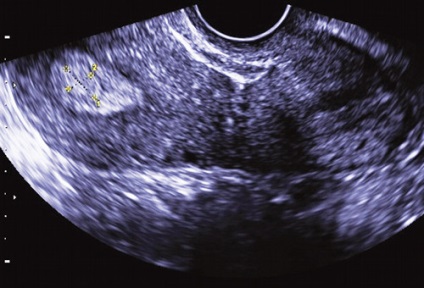

A különböző szállítási módok és a Doppler véráramlás képalkotó nedopplerovskoy valóban lehetővé teszi számunkra, hogy azonosítsuk a vaszkuláris kocsány a polip (ábra. 9), kivéve, ha nincs jele a hámlás az endometrium. Ebben az esetben a (ábra. 10) mozgását a vér az üregben a méh és a méhnyak lehet szimulálni a vér áramlását az erek a polip lábak és regisztrált a készülék kijelzőjén, mint egy hasonló színjelek.

Ábra. 10. A mozgás a vér az üregben a méh a háttérben a endometriális hiperplázia regisztrálva a CDM üzemmódban.